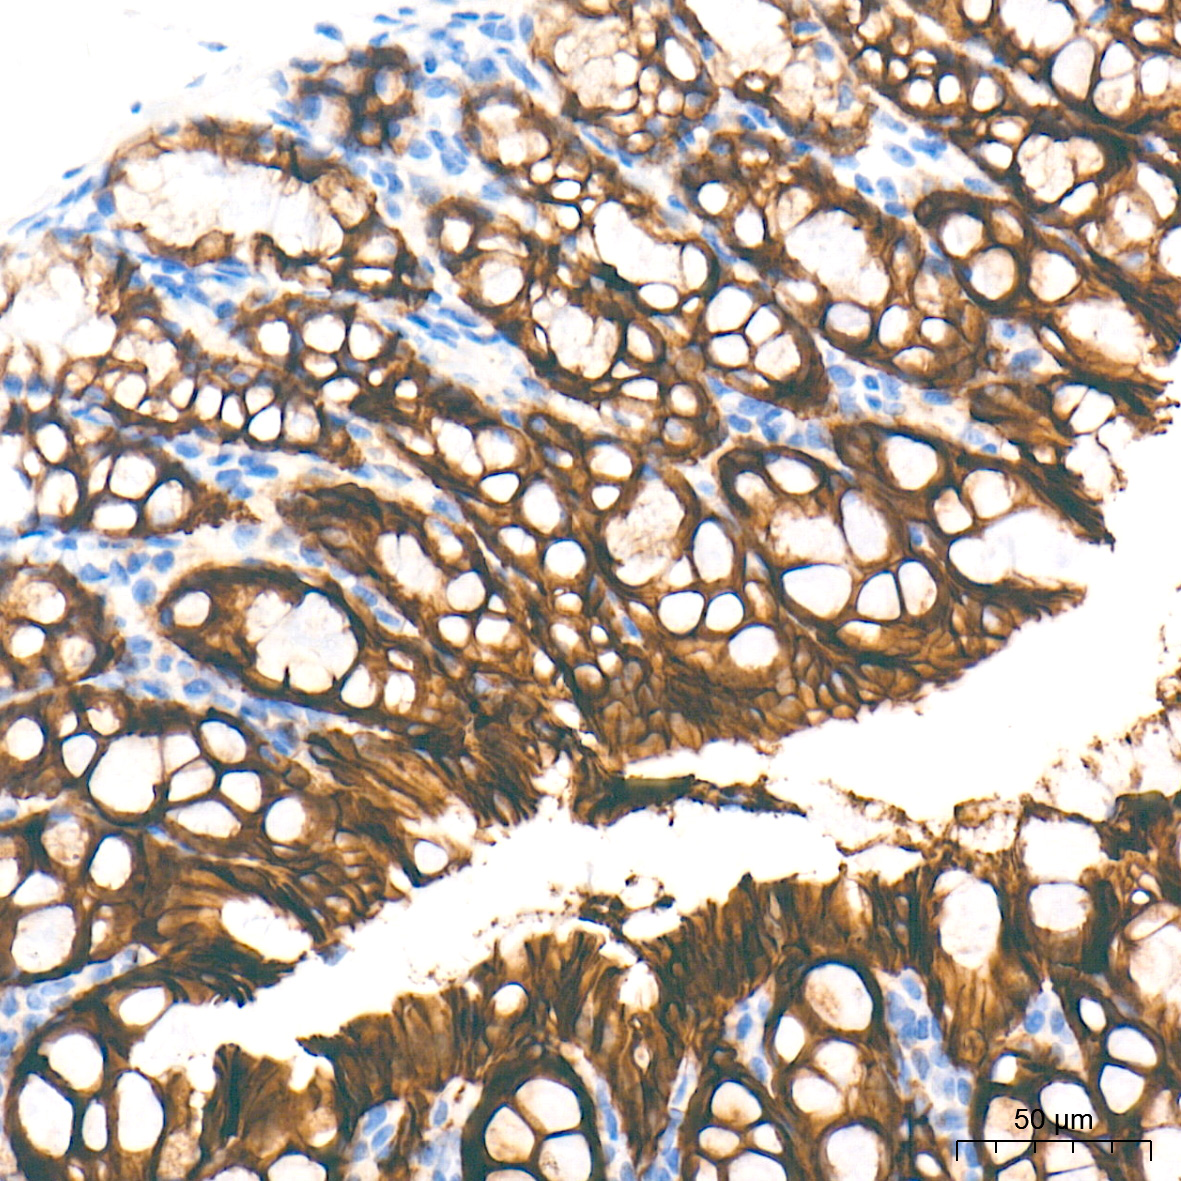

上皮-间质转化(Epithelial–mesenchymal transition, EMT)是一个生物学过程,它允许极化的上皮细胞通过基底表面与基底膜相互作用,经历多种生化变化,获得间质细胞的许多特征,包括迁移能力和侵袭性增强、对凋亡的抵抗力提高,以及细胞外基质(ECM)成分的产生大大增加。参与EMT过程控制的信号通路有:酪氨酸激酶受体(RTKs)、转化生长因子-β(TGF-β)、Notch蛋白、整联蛋白(Integrin)、WNT蛋白以及基质金属蛋白酶(MMP)等。几种细胞内在信号转导途径共同诱导EMT转录因子(ZEB,SNAIL和TWIST)的表达,具有多效性。在许多情况下,EMT所涉及的关键分子也被用作生物标志物,来鉴定EMT的发生及肿瘤的浸润和转移。